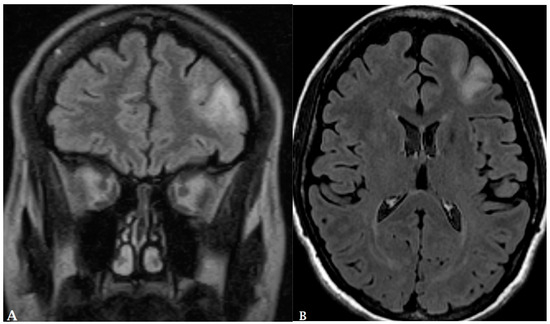

- Pepin, K.; McGee, K.; Arani, A.; Lake, D.; Glaser, K.; Manduca, A.; Parney, I.; Ehman, R.; Huston, J. MR Elastography Analysis of Glioma Stiffness and IDH1-Mutation Status. Am. J. Neuroradiol. 2018, 39, 31–36. [Google Scholar] [CrossRef] [PubMed]

- Badve, C.; Yu, A.; Dastmalchian, S.; Rogers, M.; Ma, D.; Jiang, Y.; Margevicius, S.; Pahwa, S.; Lu, Z.; Schluchter, M.; et al. MR Fingerprinting of Adult Brain Tumors: Initial Experience. Am. J. Neuroradiol. 2017, 38, 492–499. [Google Scholar] [CrossRef] [PubMed]

- de Blank, P.; Badve, C.; Gold, D.R.; Stearns, D.; Sunshine, J.; Dastmalchian, S.; Tomei, K.; Sloan, A.E.; Barnholtz-Sloan, J.S.; Lane, A.; et al. Magnetic Resonance Fingerprinting to Characterize Childhood and Young Adult Brain Tumors. Pediatr. Neurosurg. 2019, 54, 310–318. [Google Scholar] [CrossRef]

- Springer, E.; Cardoso, P.L.; Strasser, B.; Bogner, W.; Preusser, M.; Widhalm, G.; Nittka, M.; Koerzdoerfer, G.; Szomolanyi, P.; Hangel, G.; et al. MR Fingerprinting—A Radiogenomic Marker for Diffuse Gliomas. Cancers 2022, 14, 723. [Google Scholar] [CrossRef] [PubMed]